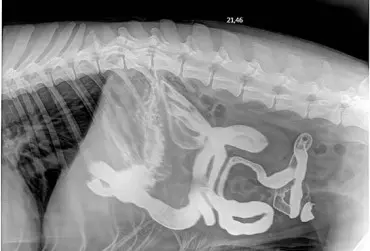

Dlaczego warto wykonywać dodatkowe badania obrazowe w diagnozowaniu chorób przewodu pokarmowego?

W praktyce weterynaryjnej jest wiele metod diagnostycznych stosowanych w chorobach przewodu pokarmowego. Takie badania jak ultrasonografia, radiografia, endoskopia, tomografia komputerowa, rezonans magnetyczny rozszerzają możliwości diagnostyczne w zrozumieniu chorób jamy brzusznej. Niektórzy pacjenci – poza badaniem klinicznym, wywiadem i badaniem krwi – przechodzą szerszą diagnostykę. Mogą mieć wykonane pojedyncze lub wielokrotne badania obrazowe. Ultrasonografia jest najbardziej popularną metodą diagnostyczną, opiera się na wysokich częstotliwościach ultradźwięków generowanych przez sondę, która poprzez komputer uwidacznia obraz naczyń krwionośnych, tkanek i narządów. Zdjęcie rentgenowskie jamy brzusznej to również typowa procedura medyczna, która pozwala na uwidocznienie kształtów i lokalizacji tkanek, narządów w jamie brzusznej. Główne zastosowanie radiografii to także choroby kości, stawów oraz diagnostyka zmian w klatce piersiowej.